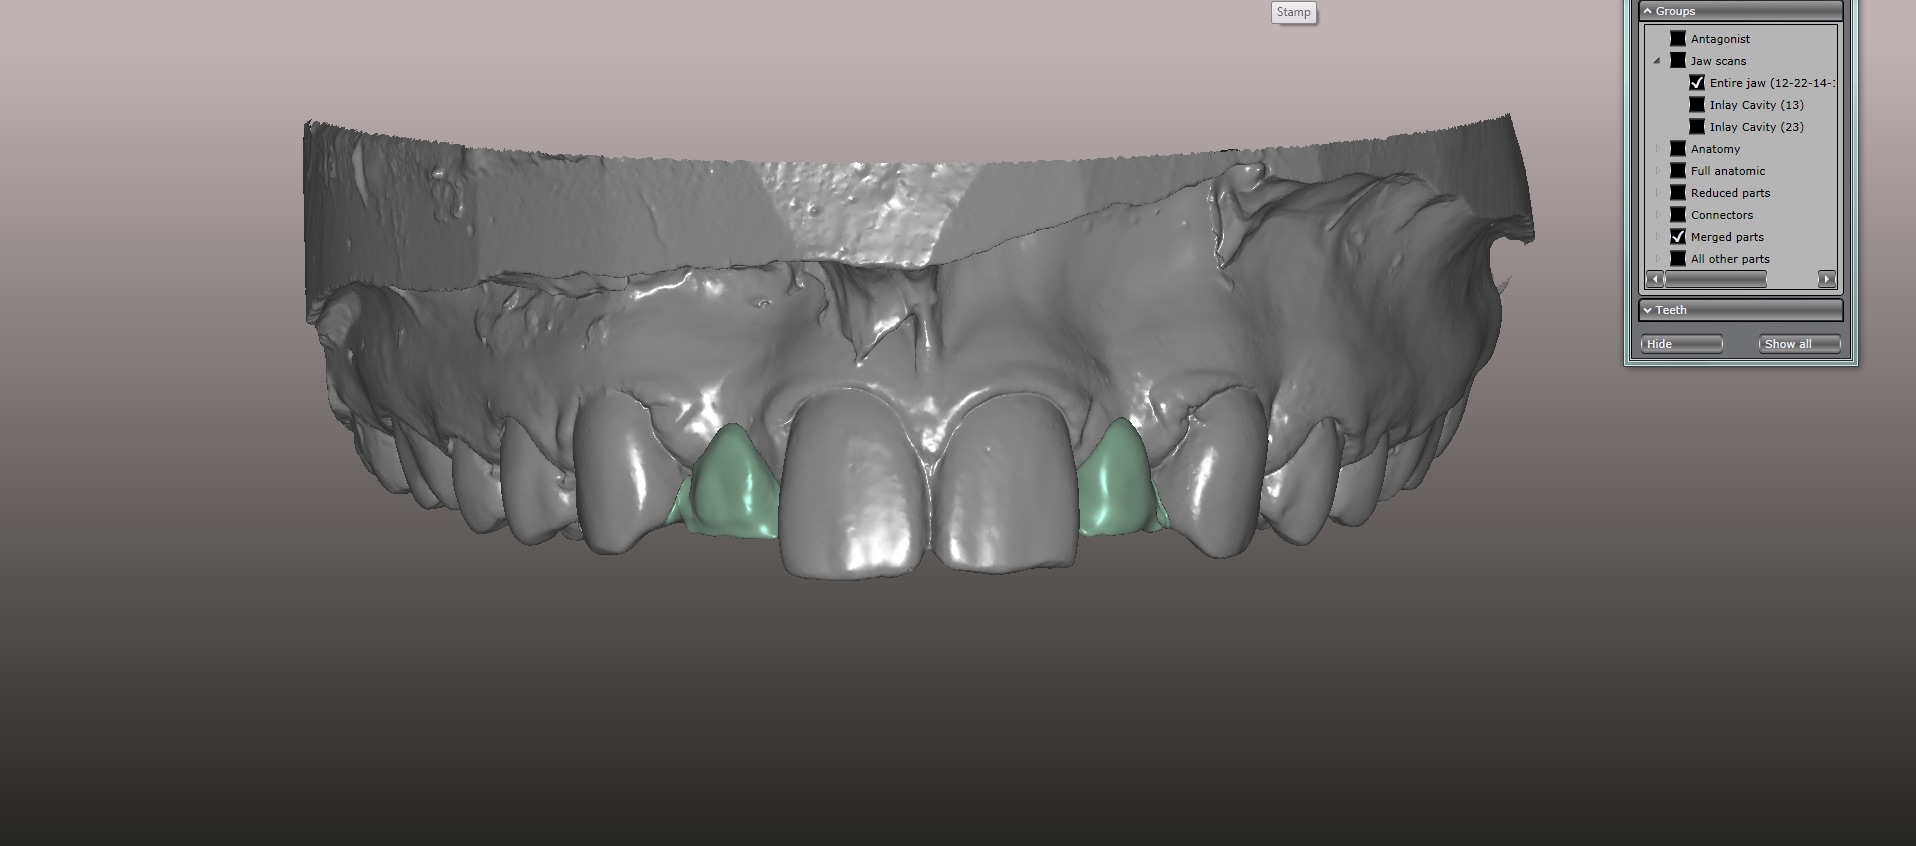

An approach utilizing CAD/CAM was employed to fabricate an accurate fitting, retentive, and esthetic ceramic single-wing resin-bonded bridge. Impressions were taken of the patient and scanned in the laboratory using maximum intensity projection. The scanned models were then used to design the final prosthetic frames utilizing EXOCAD software. The retainer positions and extensions were designed on the models based on the occlusal clearance (Figure 15). Next, the replacement tooth forms were chosen from a virtual library (Figure 16), and try-in PMMA bridge prototypes were milled in Primotec USA PMMA. This allowed for try-in of the design, adjustment of the contacts, and intraoral evaluation of the ridge contact (Figure 17). Once tried and idealized for both fit and occlusion, the design was sent back to the lab to rescan. Utilizing the software, a cut back was made on the lateral incisor (Figure 18), and a 0.3mm space was also virtually designed on the internal surface of the retainer wing to allow layering with feldspathic ceramic (Figure 19). The 0.2 mm internal edge of the wing was designed to be left intact to allow for precise seating and verification of fit on the model. After the frame was milled in zirconia (Zirconzahn, Prettau), it was verified on the model, and high fusing margin porcelain (Noritake CZR) was mixed with a clear utility wax and applied to the internal 0.3 mm depression. This was baked in the oven at a high temperature, allowing the wax to burn out and leaving the feldspathic ceramic fused to the internal surface of the retainer. Once cooled, this was checked for precise fitting on the model and adjustments were made to ensure full seating.

(15.) Models mounted in maximum intensity projection, allowing design of the retainer extensions on the lingual of the canines (in pink).

Figure 15